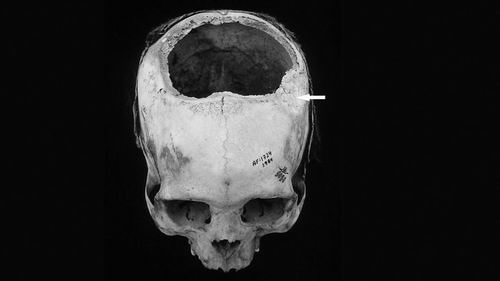

新疆考古发现的头骨穿孔现象.pdf

新疆考古发现60余个穿孔头骨